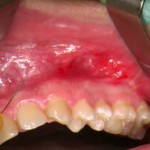

Questo interessante video presenta la realizzazione di un restauro vestibolare estetico eseguito tramite un approccio multidisciplinare che prevede la realizzazione di un lembo di...